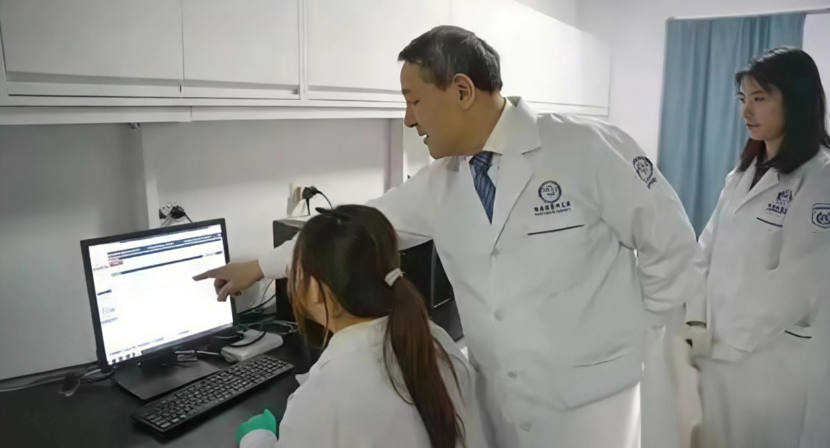

哈医大科研团队:全链条攻关 破解寒地心血管病“调控密码

哈医大科研团队:全链条攻关 破解寒地心血管病“调控密码